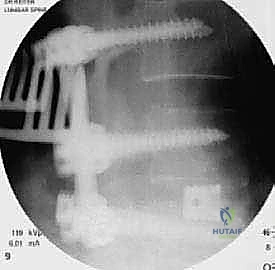

في هذه التقنية، يتم الوصول إلى العمود الفقري من الخلف مباشرة. يقوم الجراح بإزالة جزء من العظم (الصفيحة الفقرية Laminectomy) للوصول إلى القناة الشوكية. يتم سحب الأعصاب برفق إلى الجانبين للوصول إلى القرص التالف وإزالته، ثم يتم إدخال "أقفاص" (Cages) مدعومة بطعوم عظمية من كلا الجانبين.

تقنية TLIF (الاندماج الفقري القطني عبر الثقب)

تُعد TLIF تطوراً لتقنية PLIF. بدلاً من الدخول مباشرة من المنتصف وسحب الأعصاب بشكل كبير، يتم الوصول إلى القرص الغضروفي من جانب واحد عبر "الثقبة" (Foramen) - وهي الفتحة التي يخرج منها العصب.

| مسار الدخول | من الخلف مباشرة (خط الوسط). | من الجانب الخلفي (عبر الثقبة العصبية). |

| التعامل مع الأعصاب | يتطلب سحب الأعصاب (Retraction) من الجانبين. | يتطلب سحباً ضئيلاً للعصب من جانب واحد فقط. |

| عدد الأقفاص (Cages) | يتم وضع قفصين (واحد في كل جانب). | يتم وضع قفص واحد كبير مائل. |

الخطوة 4: زراعة القفص والطعم العظمي (Cage Insertion)

يتم إدخال قفص مصنوع من مادة PEEK أو التيتانيوم، مملوء بطعم عظمي (يؤخذ غالباً من المريض نفسه أو طعم صناعي)، في المساحة الفارغة. هذا القفص يعيد الارتفاع الطبيعي للفقرات ويخفف الضغط عن منافذ الأعصاب.